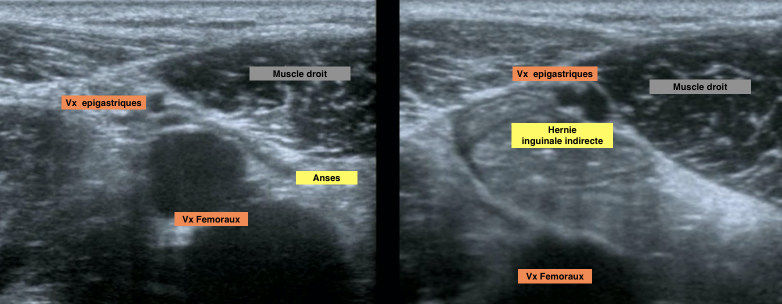

Coupe standard

Ne pas confondre avec le cordon spermatique qui part entre deux

En vrai il y a 2 veines épigastriques inf

Hernie inguinale indirecte

Hernie inguinale directe

Diagnostic differentiel

- Suspect si

- Pas de peristaltisme

- Pas de changement au valsalva

- DD

- Contenu graisseux

- Masse du cordon spermatique

- Adenopathie